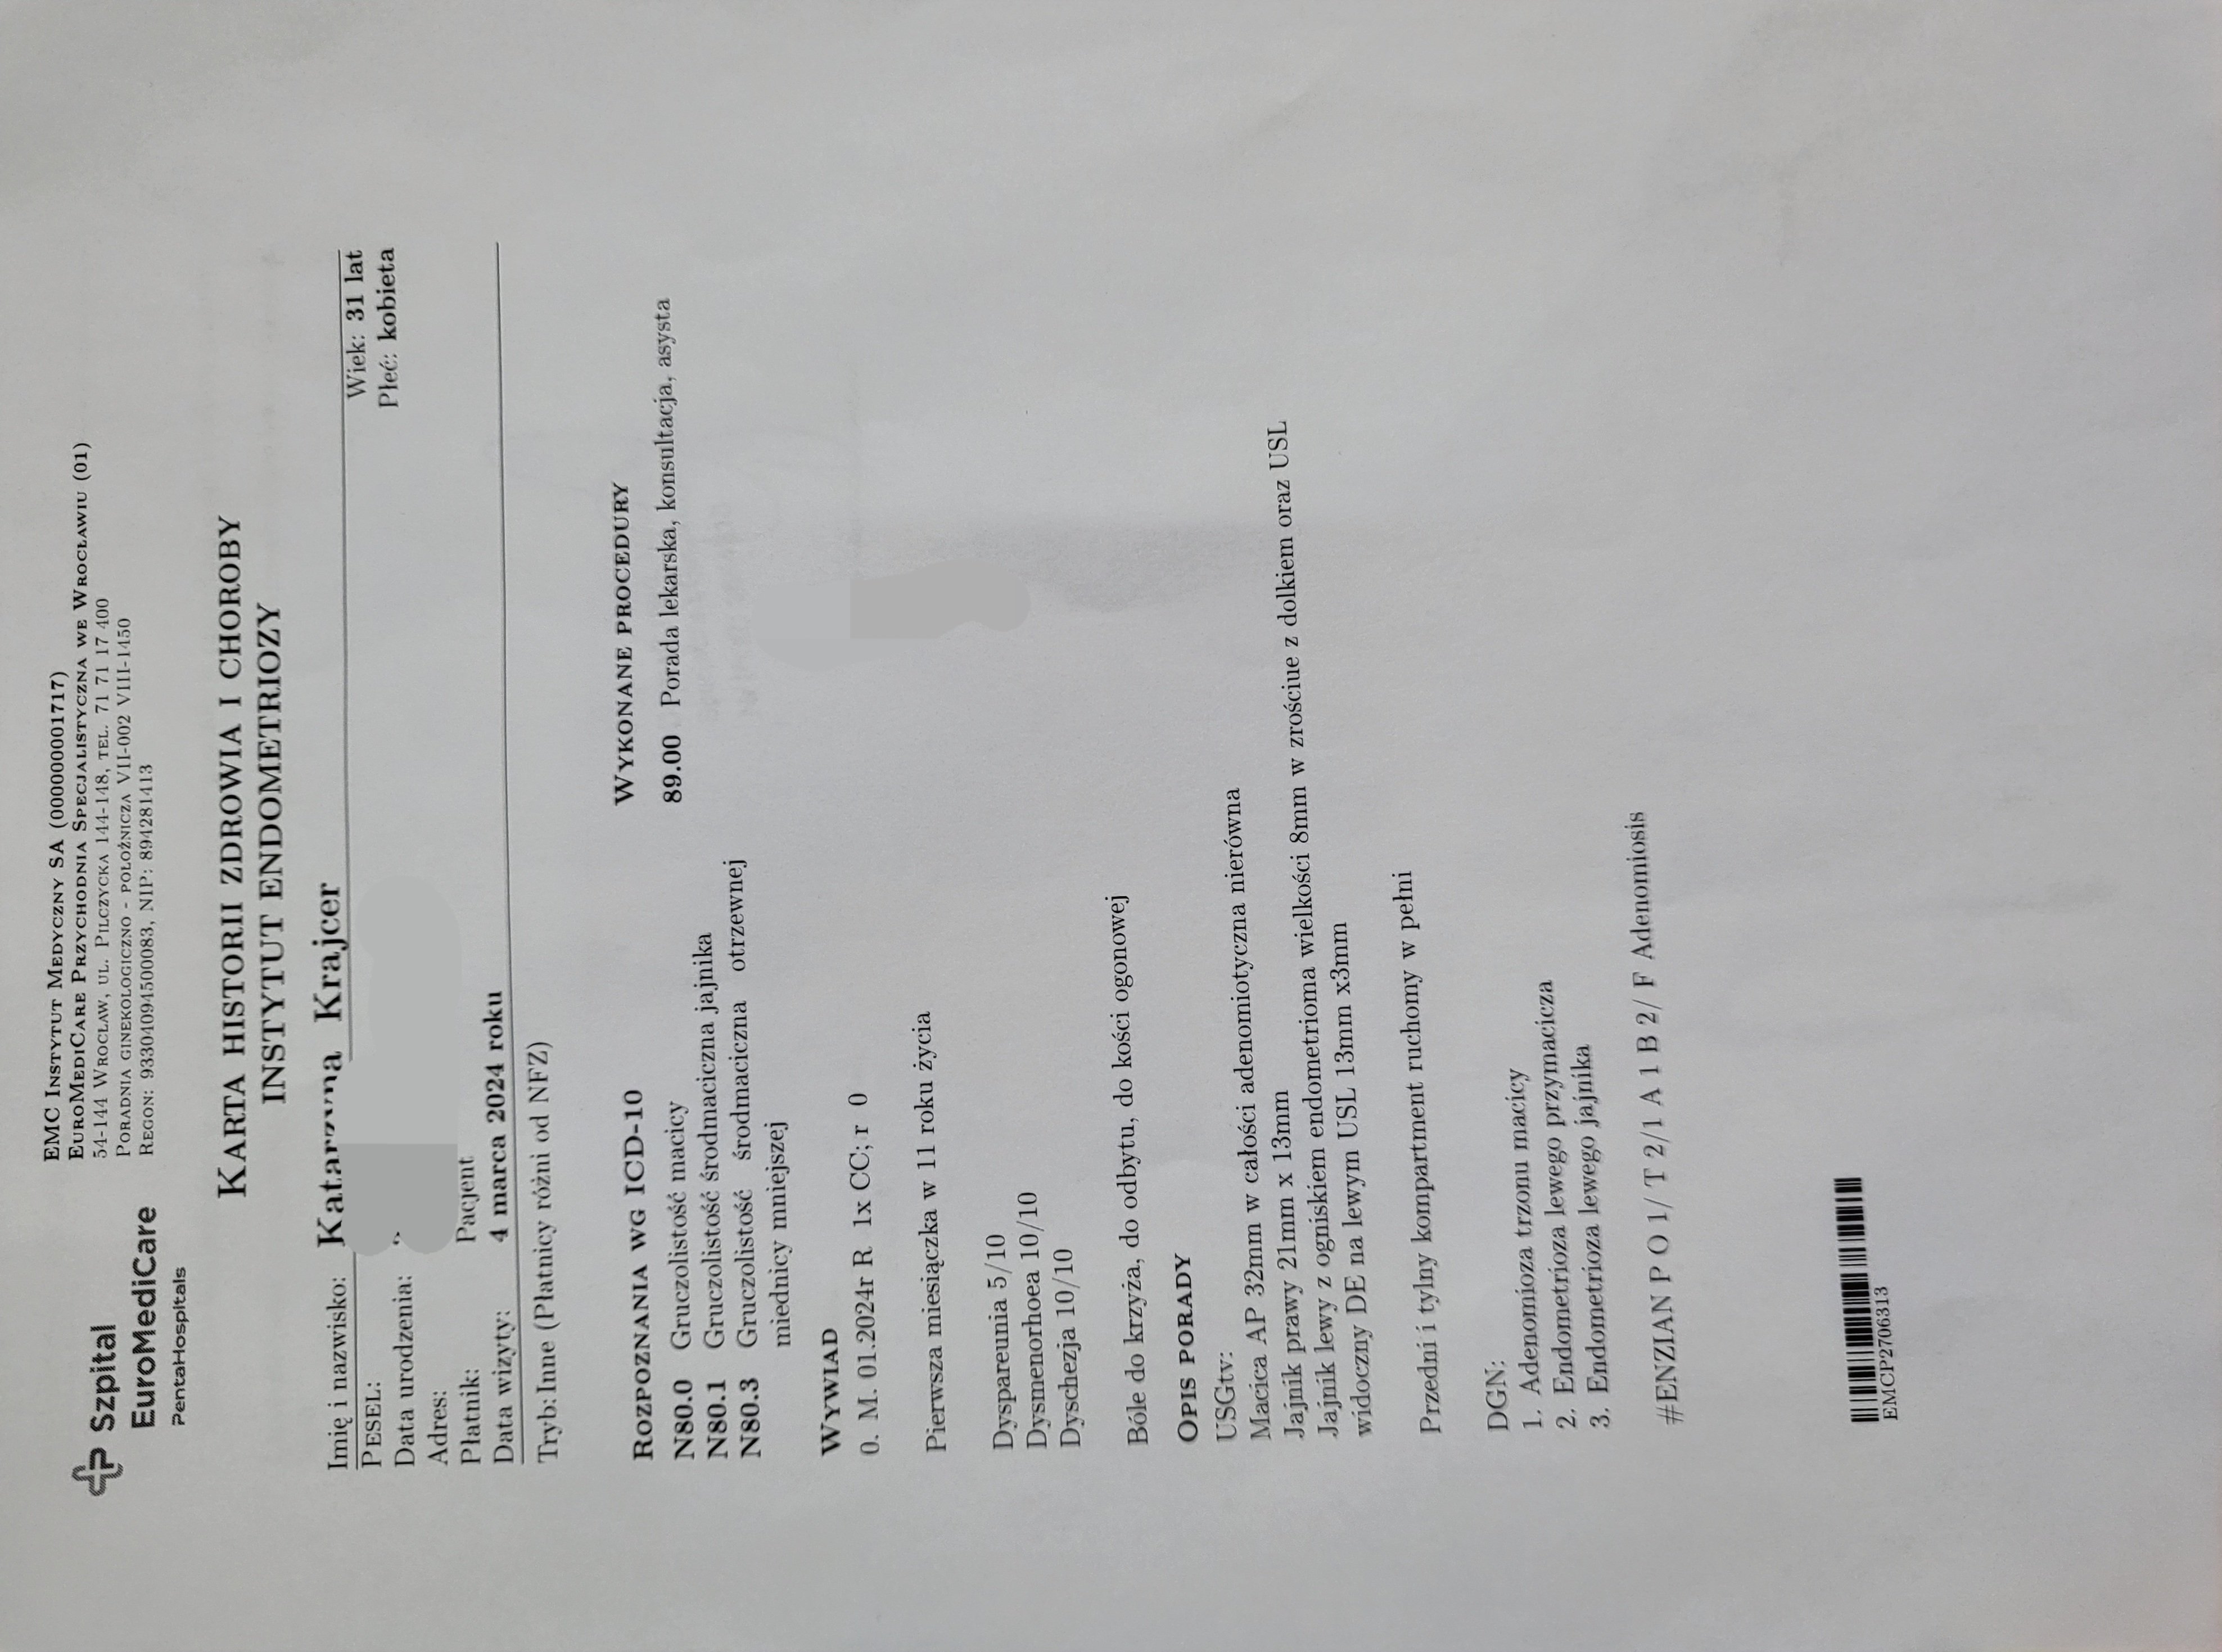

Dr Mikołaj Karmowski – ginekolog specjalista w dziedzinie leczenia endometriozy, postawił diagnozę endometrioza i adenomioza.

Postanowiłam umówić się na wizytę, która miała miejsce 04.03.2024r.

Dr Karmowski prosił, abym usiadła na fotelu i po dokładnym przeprowadzeniu badania opowiedział o wszystkim co mi dolegało. W końcu na swojej drodze spotkałam lekarza, który chce i potrafi mi pomóc.

Po wizycie w Instytucie Endometriozy zdecydowałam się napisać informacje swojej ginekolog o endometriozie i adenomiozie oraz o konieczności usunięcia całej macicy wraz z lewym jajnikiem.